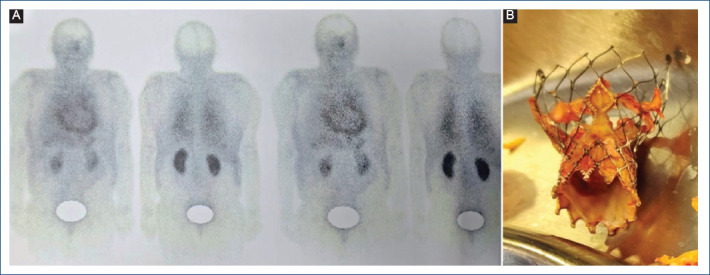

Staphylococcus lugdunensis endocarditis causing prosthetic aortic valve dysfunction after TAVR.